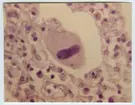

'Mikroskopbilder på amöba: :: Text på baksidan av fotot: ''Balantidium coli attached to surface of intestinal mucous membrane x 1200. 9910-1.15'' :: :: Ingår i serie med fotonr. 5653:1-16.'

'Mikroskopbilder på amöba: :: Text på baksidan av fotot: ''Haematophagous Entamoeba histolytica in a section of intestinal mucous membrane showing red cells in various stages of digestion by the parasite x 2000. 85--1.65.'' :: :: Ingår i serie med fotonr. 5653:1-16.'